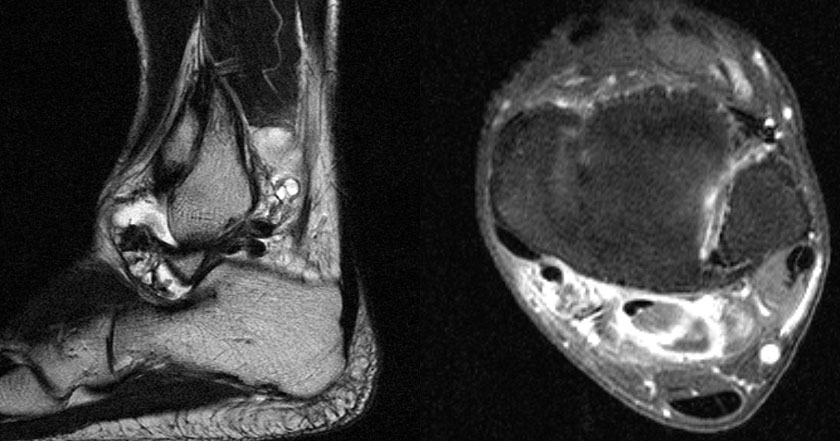

Die Magnetresonanztomographie erlaubt nicht nur die exakte Beurteilung der intramedul­lären und extraossären Tumorausdehnung einschließlich reaktiver Zone, sondern auch die genaue Lagebeziehung zu neurovaskulären Strukturen (Abb. 8) und eine Differenzierung zwischen vitalen versus nekrotischen Tumoranteilen. Dies ist insbesondere für eine mögliche Biopsie von entscheidender Bedeutung um repräsentatives Tumorgewebe für die histo­patho­logische Analyse gewinnen zu können. Die bei Verdacht auf einen Knochen- oder Weichteiltumor vom Radiologen durchzuführenden Standardprotokolle der MRT wurden im Jahr 2006 von der Arbeitsgemeinschaft Muskuloskelettale Diagnostik der Deutschen Röntgengesellschaft veröffentlicht (Tab.2) und gewähren bei entsprechender Umsetzung eine qualitativ hochwertige Untersuchung (DRG, 2006).

MR-tomographische Darstellung eines unspezifischen weichteiligen Raumforderug im Bereich des dorso-lateralen Rückfußes. Die offene Probebiopsie ergab schließlich die Diagnose eines hochmalignen Synovialsarkoms.

Abbildung 34